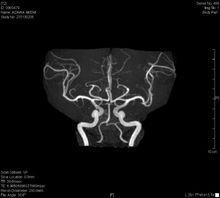

日本癌症治療機構配備有最先進的儀器,專業醫生的權威診斷,以早期發現癌病變為優勢,有效控制癌症病情的變化。同時,日本的風光名勝聞名世界,來診者不但可觀光日本美景、體驗日本風情,更可以在日本接受世界領先的醫療技術和設施治療,有效的發現和治療300多種癌症,使每一名癌症患者都能得到最及時的治療和最好的恢復,早日享受健康舒適的美好人生。